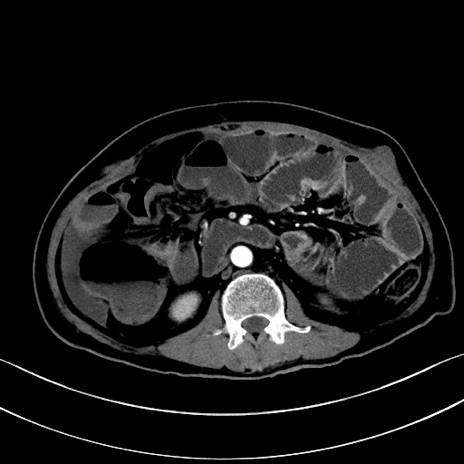

症例28(横断像)

【症例】60歳代男性

【主訴】嘔吐

【現病歴】胃癌にて胃全摘後。食思不振が悪化し、夜中に嘔吐することがある。

【既往歴】胃癌、胃全摘、脾摘、胆摘後

【データ】WBC 5900、CRP 10.56